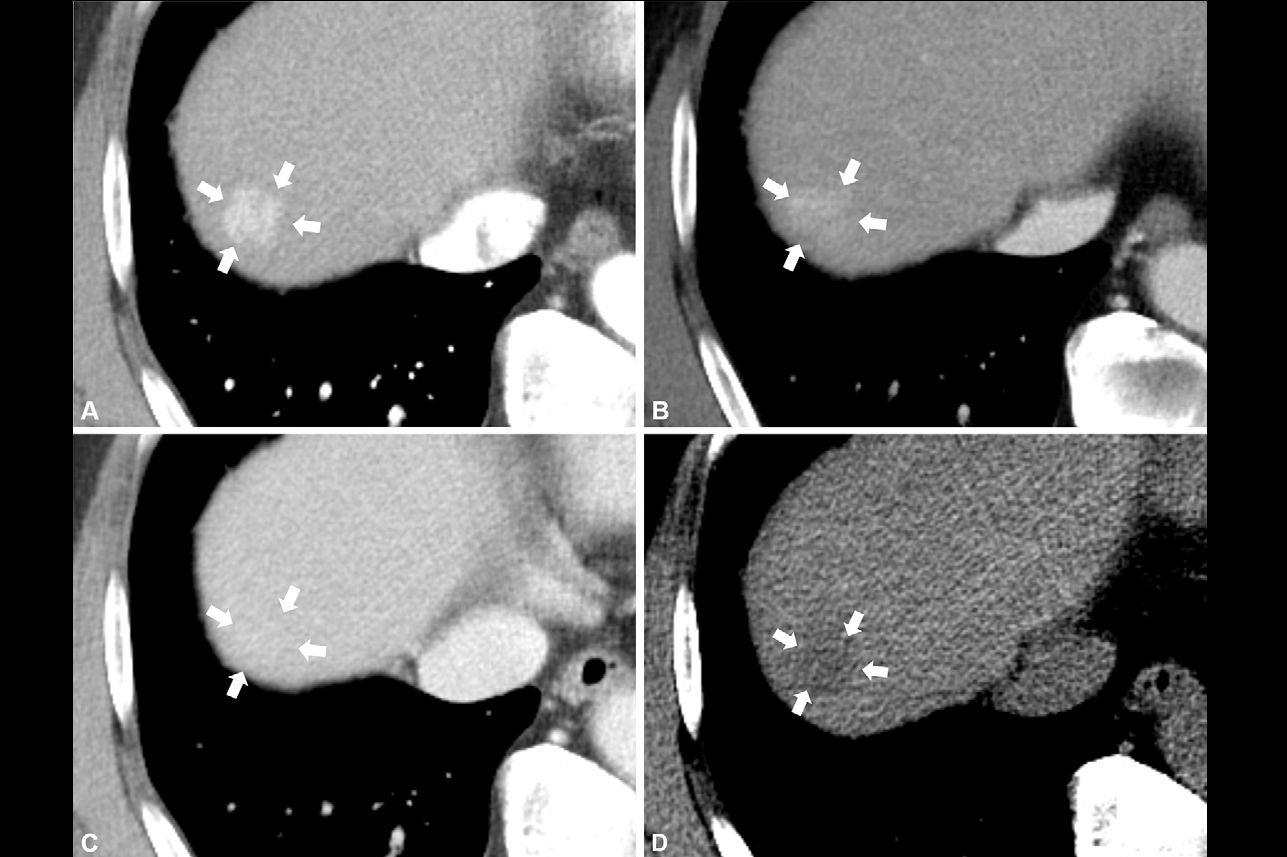

Polvieng and colleagues conducted a study that explored the prognostic impact of sarcopenia (i.e., loss of muscle mass) on overall survival, disease-free survival, and postoperative outcomes among patients with hepatocellular carcinoma who underwent surgery. The work included 83 patients with liver cancer who had surgery and preoperative abdominal CT between January 2010 and December 2020; the team identified sarcopenia by assessing skeletal muscle mass of the third lumbar vertebra using CT imaging and software analysis. Cutoffs for skeletal muscle index were 43.75 cm2/m2 for men and 41.10 cm2/m2 for women.